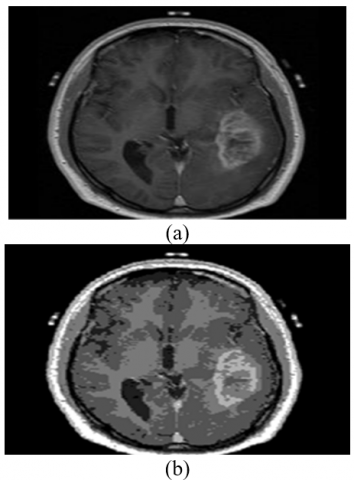

The median filter collects only the important pixel when a window is slide over the input image which was very helpful in removing the patient artifacts from the images [16-20]. It mainly removes the salt and pepper type noise from the given image. The output of the median filter is shown in Figure 1.

Figure 1. (a) The input image given to median filter, (b) The output of the median filter with no artifacts